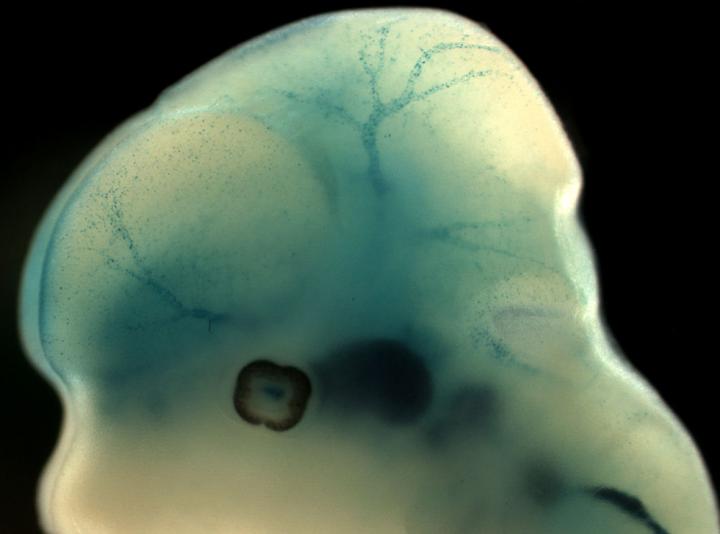

Studies on mice reveal that a special protein in the brain's tiniest blood vessels may affect the risk of stroke. Peter Carlsson, professor in genetics at the University of Gothenburg, and his research team are publishing new research findings in the journal Developmental Cell about how the blood-brain barrier develops and what makes the capillaries in the brain different from small blood vessels in other organs.

The brain's smallest blood vessels differ from those in other organs in that the capillary walls are much more compact. The nerve cells in the brain get the nutrients they need by molecules actively being transported from the blood, instead of passively leaking out from the blood vessels.

This blood-brain barrier is vital, because it enables strict control over the substances with which the brain's nerve cells come into contact. It has a protective function that if it fails, increases the risk of stroke and other complications.

Special cell type essential to development The smallest blood vessels, the capillaries, have a type of cell called pericytes. These are essential to the development of the blood-brain barrier. Pericytes are also found in other organs, and researchers have previously been unable to find out what gives the brain's pericytes this unique ability.

The Gothenburg research team has found that the brain's pericytes contain a protein, FoxF2, which is not present in the pericytes of other organs, and which coordinates the changes that make the blood vessels compact. FoxF2 is needed in order for the blood-brain barrier to form during foetal development.